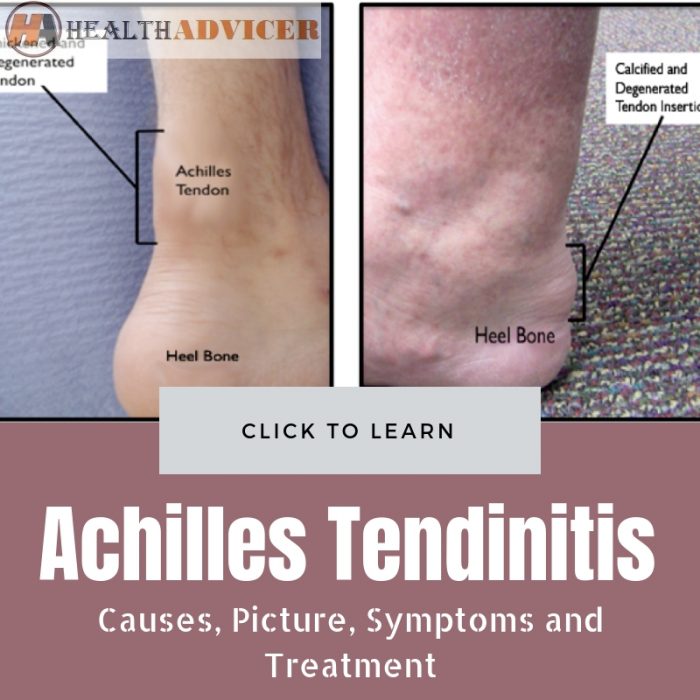

Achilles Tendinitis: Causes, Picture, Symptoms And Treatment